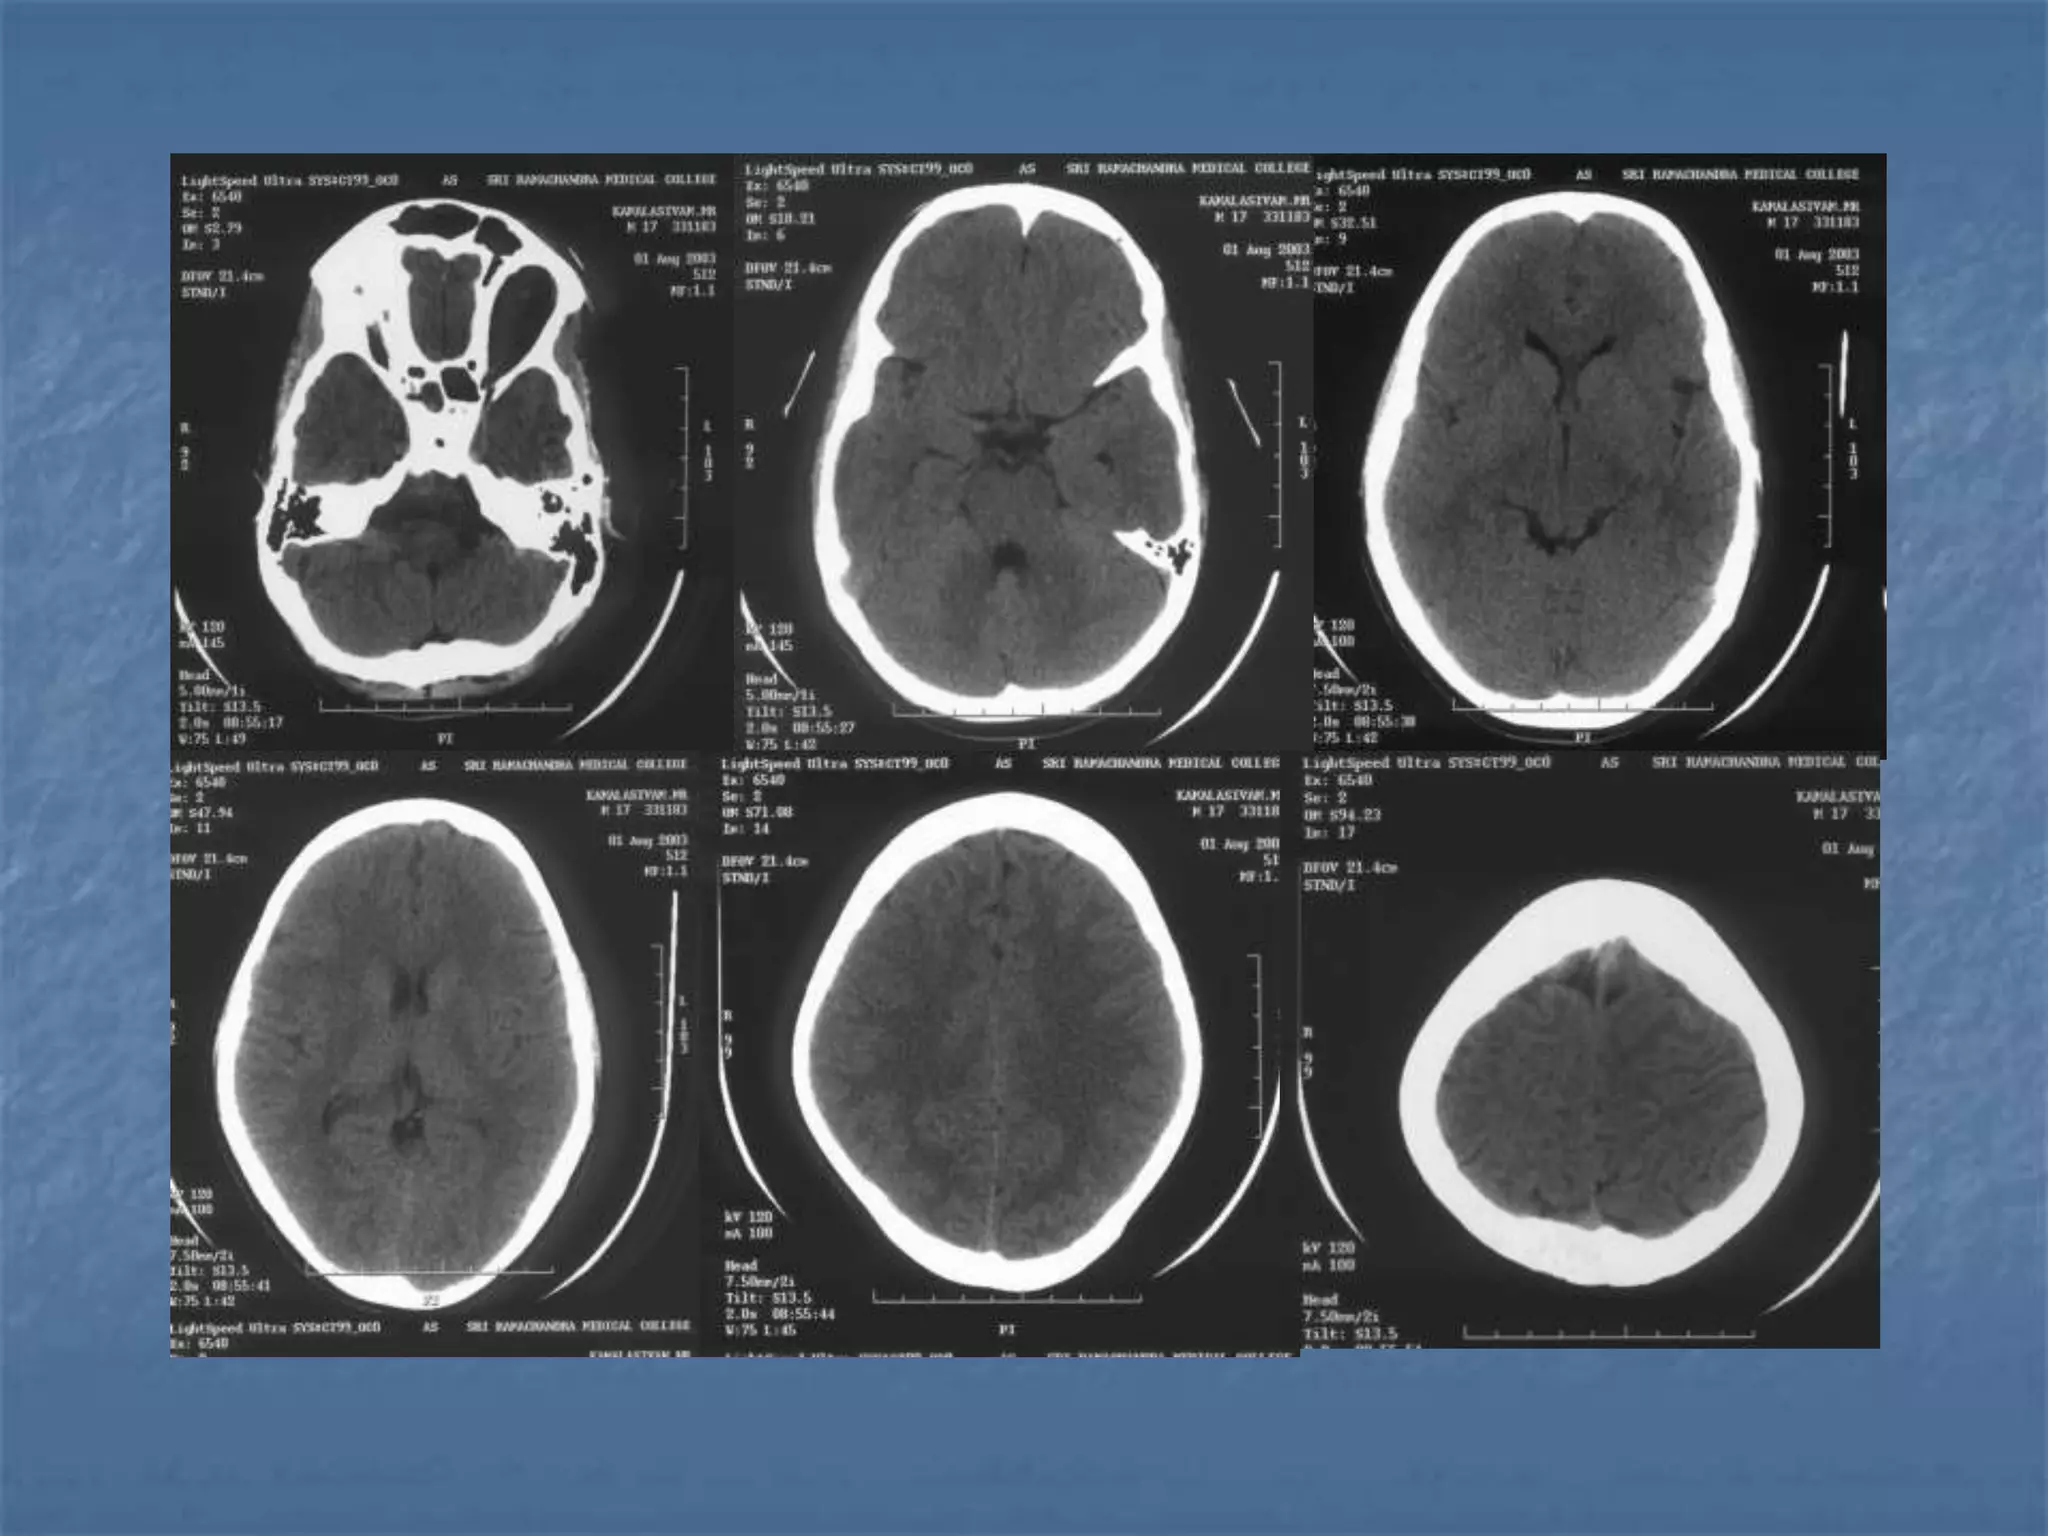

Diffuse Axonal Injury

 Diffuse axonal injury is often referred to as "shear injury". It is the most

common cause of significant morbidity in CNS trauma. Fifty percent of all

primary intra-axial injuries are diffuse axonal injuries. Acceleration,

deceleration and rotational forces cause portions of the brain with

different densities to move relative to each other resulting in the

deformation and tearing of axons. Immediate loss of consciousness is

typical of these injuries. The CT of a patient with diffuse axonal injury may

be normal despite the patient's presentation with a profound neurological

deficit. With CT, diffuse axonal injury may appear as ill-defined areas of

high density or hemorrhage in characteristic locations. The injury occurs in

a sequential pattern of locations based on the severity of the trauma. The

following list of diffuse axonal injury locations is ordered with the most

likely location listed first followed by successively less likely locations:

- Subcortical white matter

- Posterior limb internal capsule

- Corpus callosum

- Dorsolateral midbrain